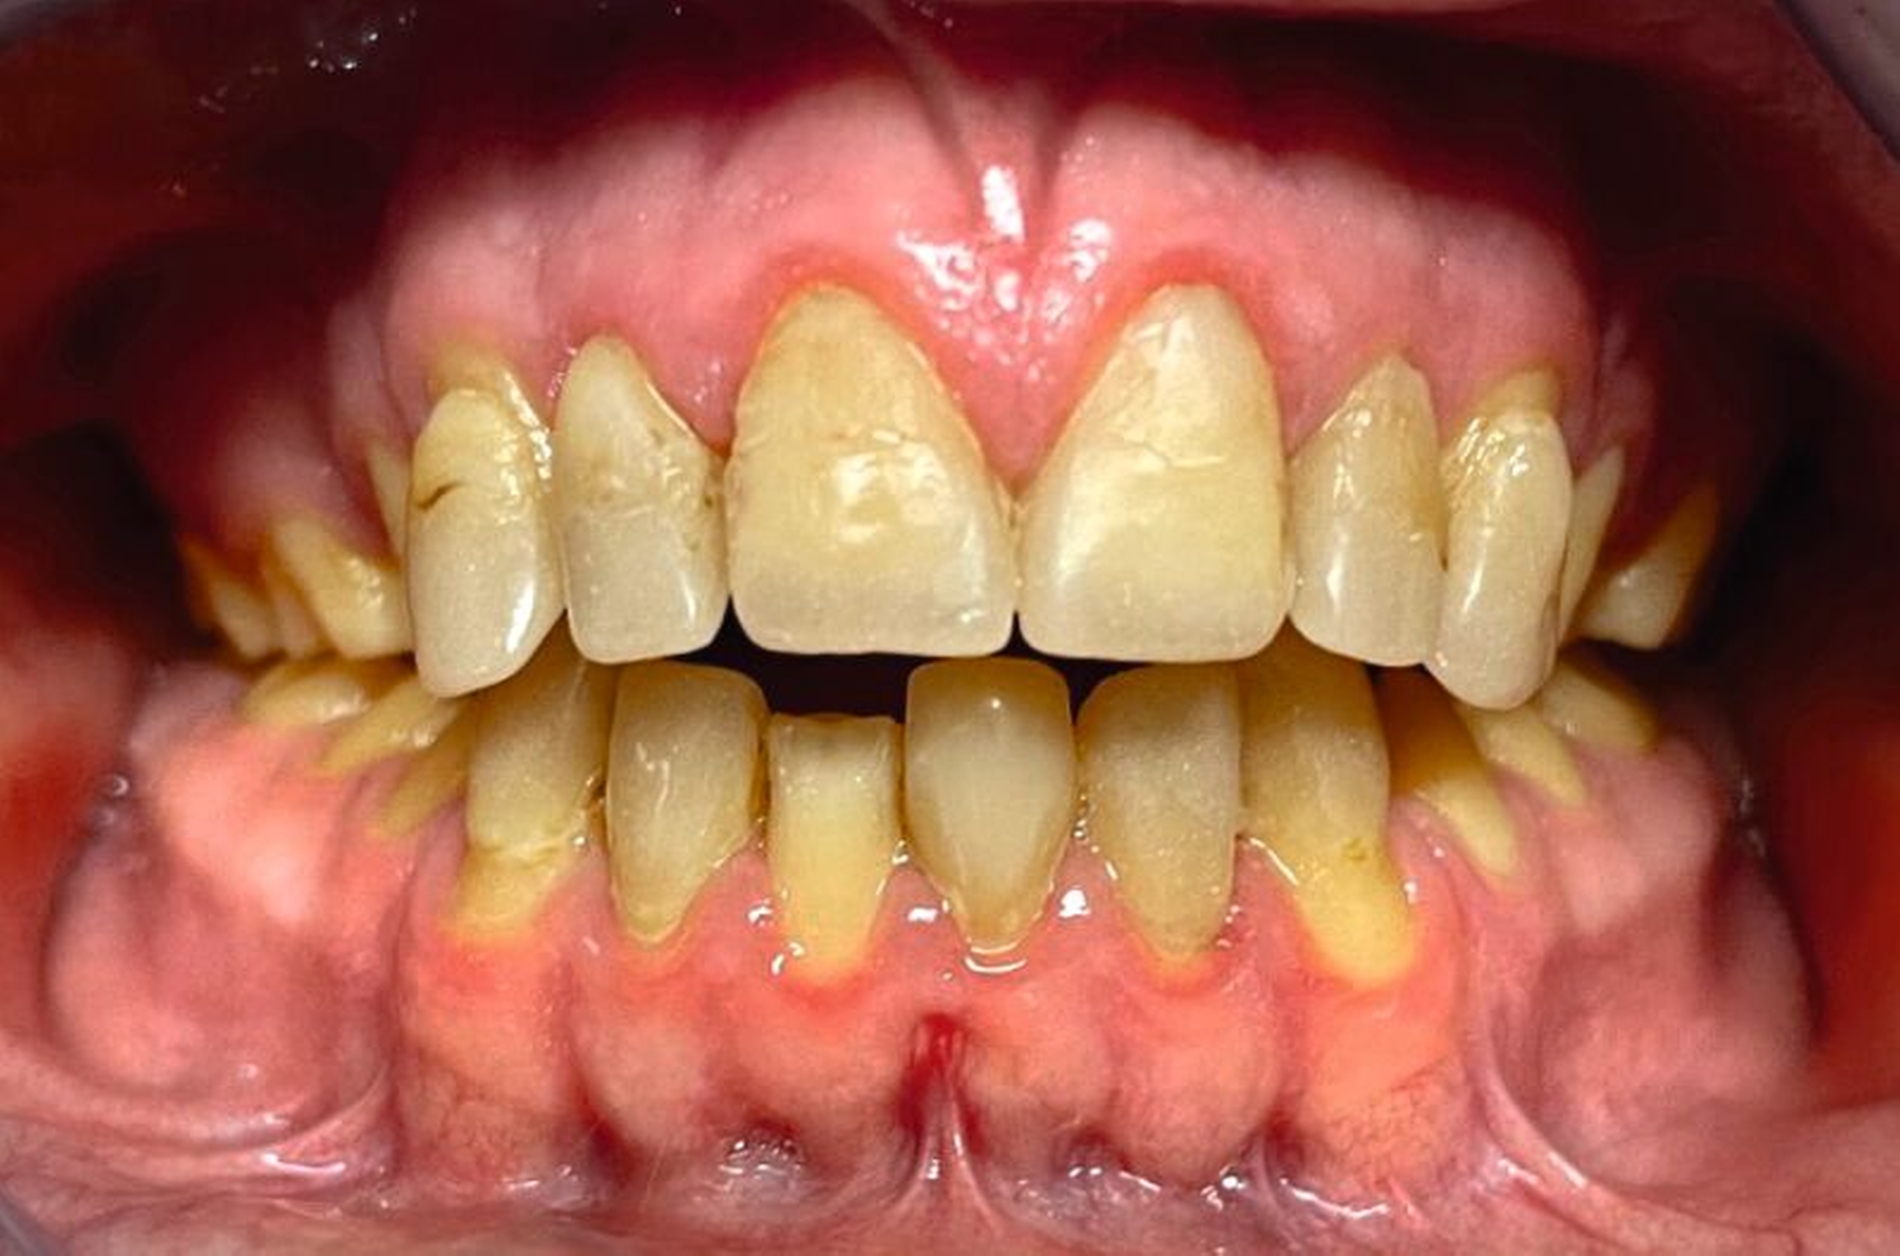

Klinisch zeigte sich ein kariöses Wechselgebiss mit generalisierten Verfärbungen und rauer Schmelzoberfläche. Mehrere Milch- und bleibende Zähne wiesen aktive kariöse Läsionen auf. Zahn 64 war zusätzlich druckdolent und gelockert, mit einer vestibulären Schwellung der Gingiva. Zudem bestanden eine Mittellinienabweichung, ein Overbite von vier Millimetern und ein Overjet von elf Millimetern (Abbildung 1). Extraoral fiel ein fliehendes Kinn mit inkomplettem Lippenschluss und hyperaktivem Musculus mentalis auf. Röntgenologisch waren alle Zähne angelegt, der Zahnschmelz zeigte jedoch eine reduzierte Opazität (Abbildung 2). Eine genetische Abklärung wurde von den Erziehungsberechtigten aus ethischen Gründen abgelehnt.

Klinisch zeigten sich ein nicht-kariöses Wechselgebiss mit generalisierter Schmelzhypoplasie an allen Zähnen sowie eine insuffiziente Mundhygiene. Zusätzlich bestanden eine fehlende Mittellinienübereinstimmung, ein Overbite von minus vier Millimetern und ein Overjet von sechs Millimetern (Abbildung 5), die sich phonetisch in einem interdentalen Sigmatismus äußerten. Röntgenologisch waren alle Zähne angelegt, jedoch war der Zahnschmelz stark reduziert oder vollständig fehlend (Abbildung 6).